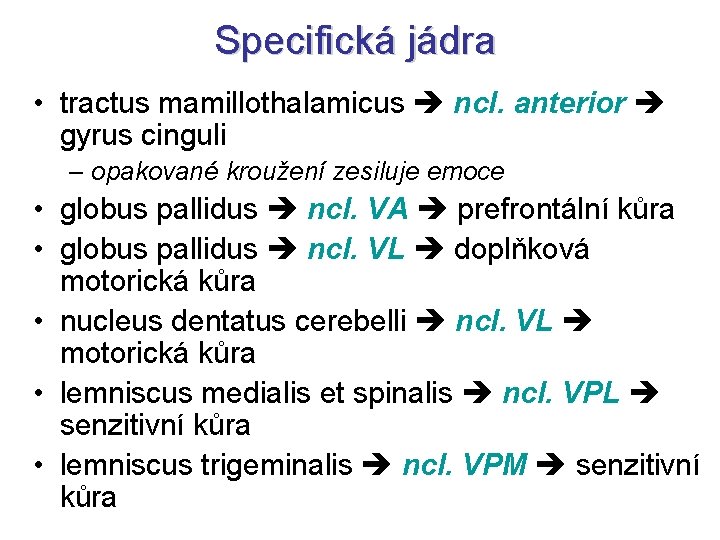

Specifická jádra • tractus mamillothalamicus ncl. anterior gyrus cinguli – opakované kroužení zesiluje emoce • globus pallidus ncl. VA prefrontální kůra • globus pallidus ncl. VL doplňková motorická kůra • nucleus dentatus cerebelli ncl. VL motorická kůra • lemniscus medialis et spinalis ncl. VPL senzitivní kůra • lemniscus trigeminalis ncl. VPM senzitivní kůra